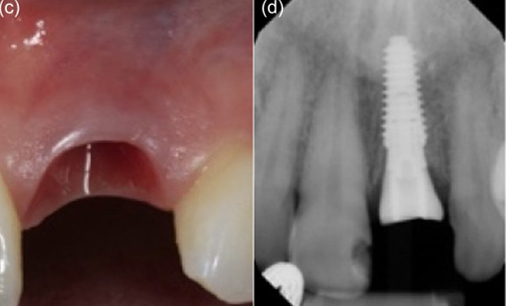

Minimally invasive removal of fractured central incisor and placement of immediate implant (Megagen Anyridge) without osteotomy on Patient 1: (a) Immediate prepless immediate implant on central incisor. (b) Anatomical healing abutment placed. (c) Transmucosal tunnel and emergence profile development by anatomical healing abutment. (d) Peri‐apical radiograph on the day of implant placement with anatomic healing abutment. (e) Peri‐apical radiograph with final restoration at 12 months. (f) Definitive monolithic Zr restoration.